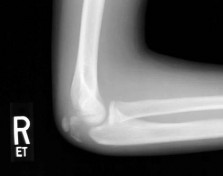

(SAE11AN.11) A 28-year-old man has decreased finger proximal interphalangeal (PIP) joint range of motion afte…